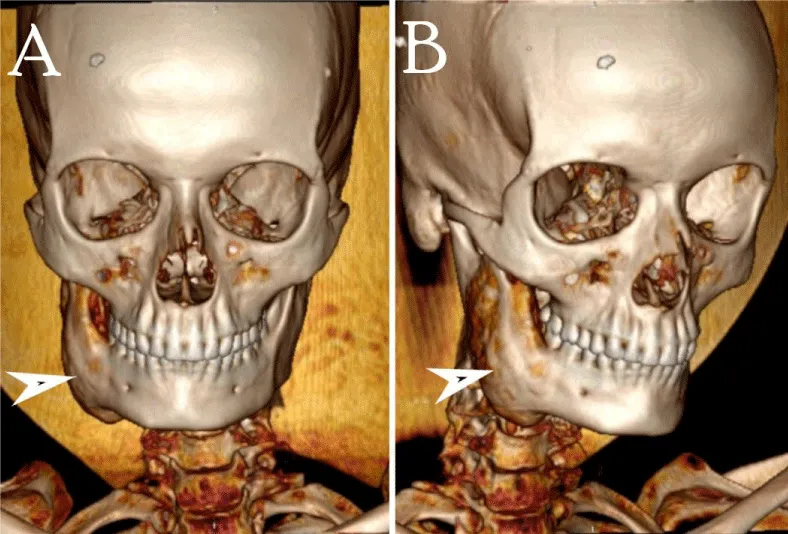

On examination, extra-orally a well-defined swelling on the right side of the face in the region of ramus and body of mandible resulting in facial asymmetry with normal smooth intact overlying skin (Figure 1). It measured about 6.0×4.3 cm hard in consistency and non-tender on palpation. There was no evidence of lymphadenopathy on either side of the neck. On intra-oral examination, there was a significant expansion of ramus and body of right mandible extending up to the right lower molar tooth causing obliteration of buccal vestibule with redness of overlying mucosa. There was no evidence of pussy discharge at the site of swelling (Figure 2).

CT scan with contrast was recommended to elicit the extent of the lesion and to characterize the radiological features. It showed a large well corticated, sharply marginated mixed density expansile lesion involving the ramus and body of mandible reaching up to the root of the right lower molar tooth. There was no evidence of cortical break, destruction, or erosion of involved bone. Few intra-lesional hyperdense areas were seen representing calcific foci/ cementing material (Figures 4-6).